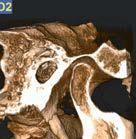

Nell’ambito della radiologia 3D ortopedica, il centro diagnostico utilizza il nuovissimo macchinario NewTom 5G XL, in grado di individuare con la massima precisione la presenza di fratture o lussazioni delle articolazioni, controllare la corretta guarigione di una frattura, valutare una lesione o una ferita causata da infezione, artrite o crescita anormale dell’osso.

Il tutto mediante una semplice e veloce scansione, grazie alla quale si otterranno diverse immagini in 3D ad altissima risoluzione e, per ottenere immagini ancora più nitide mediante un bassissimo dosaggio di radiazioni, gli esperti si avvalgono dell’innovazione racchiusa nella tecnologia Cone Beam.

Se con la radiologia tradizionale era necessario eseguire scansioni multiple, la novità introdotta dal macchinario NewTom 5G XL risiede nella capacità di fornire immagini ad alta risoluzione in un’unica scansione, mostrando nitidamente i dettagli delle articolazioni degli arti superiori e inferiori. Inoltre, a differenza della tecnologia 2D, la radiologia 3D ortopedica permette di individuare immediatamente alcune patologie come quella del metatarso, la quale richiede un allineamento visivo dedicato o una diagnosi delle micro fratture ossee.